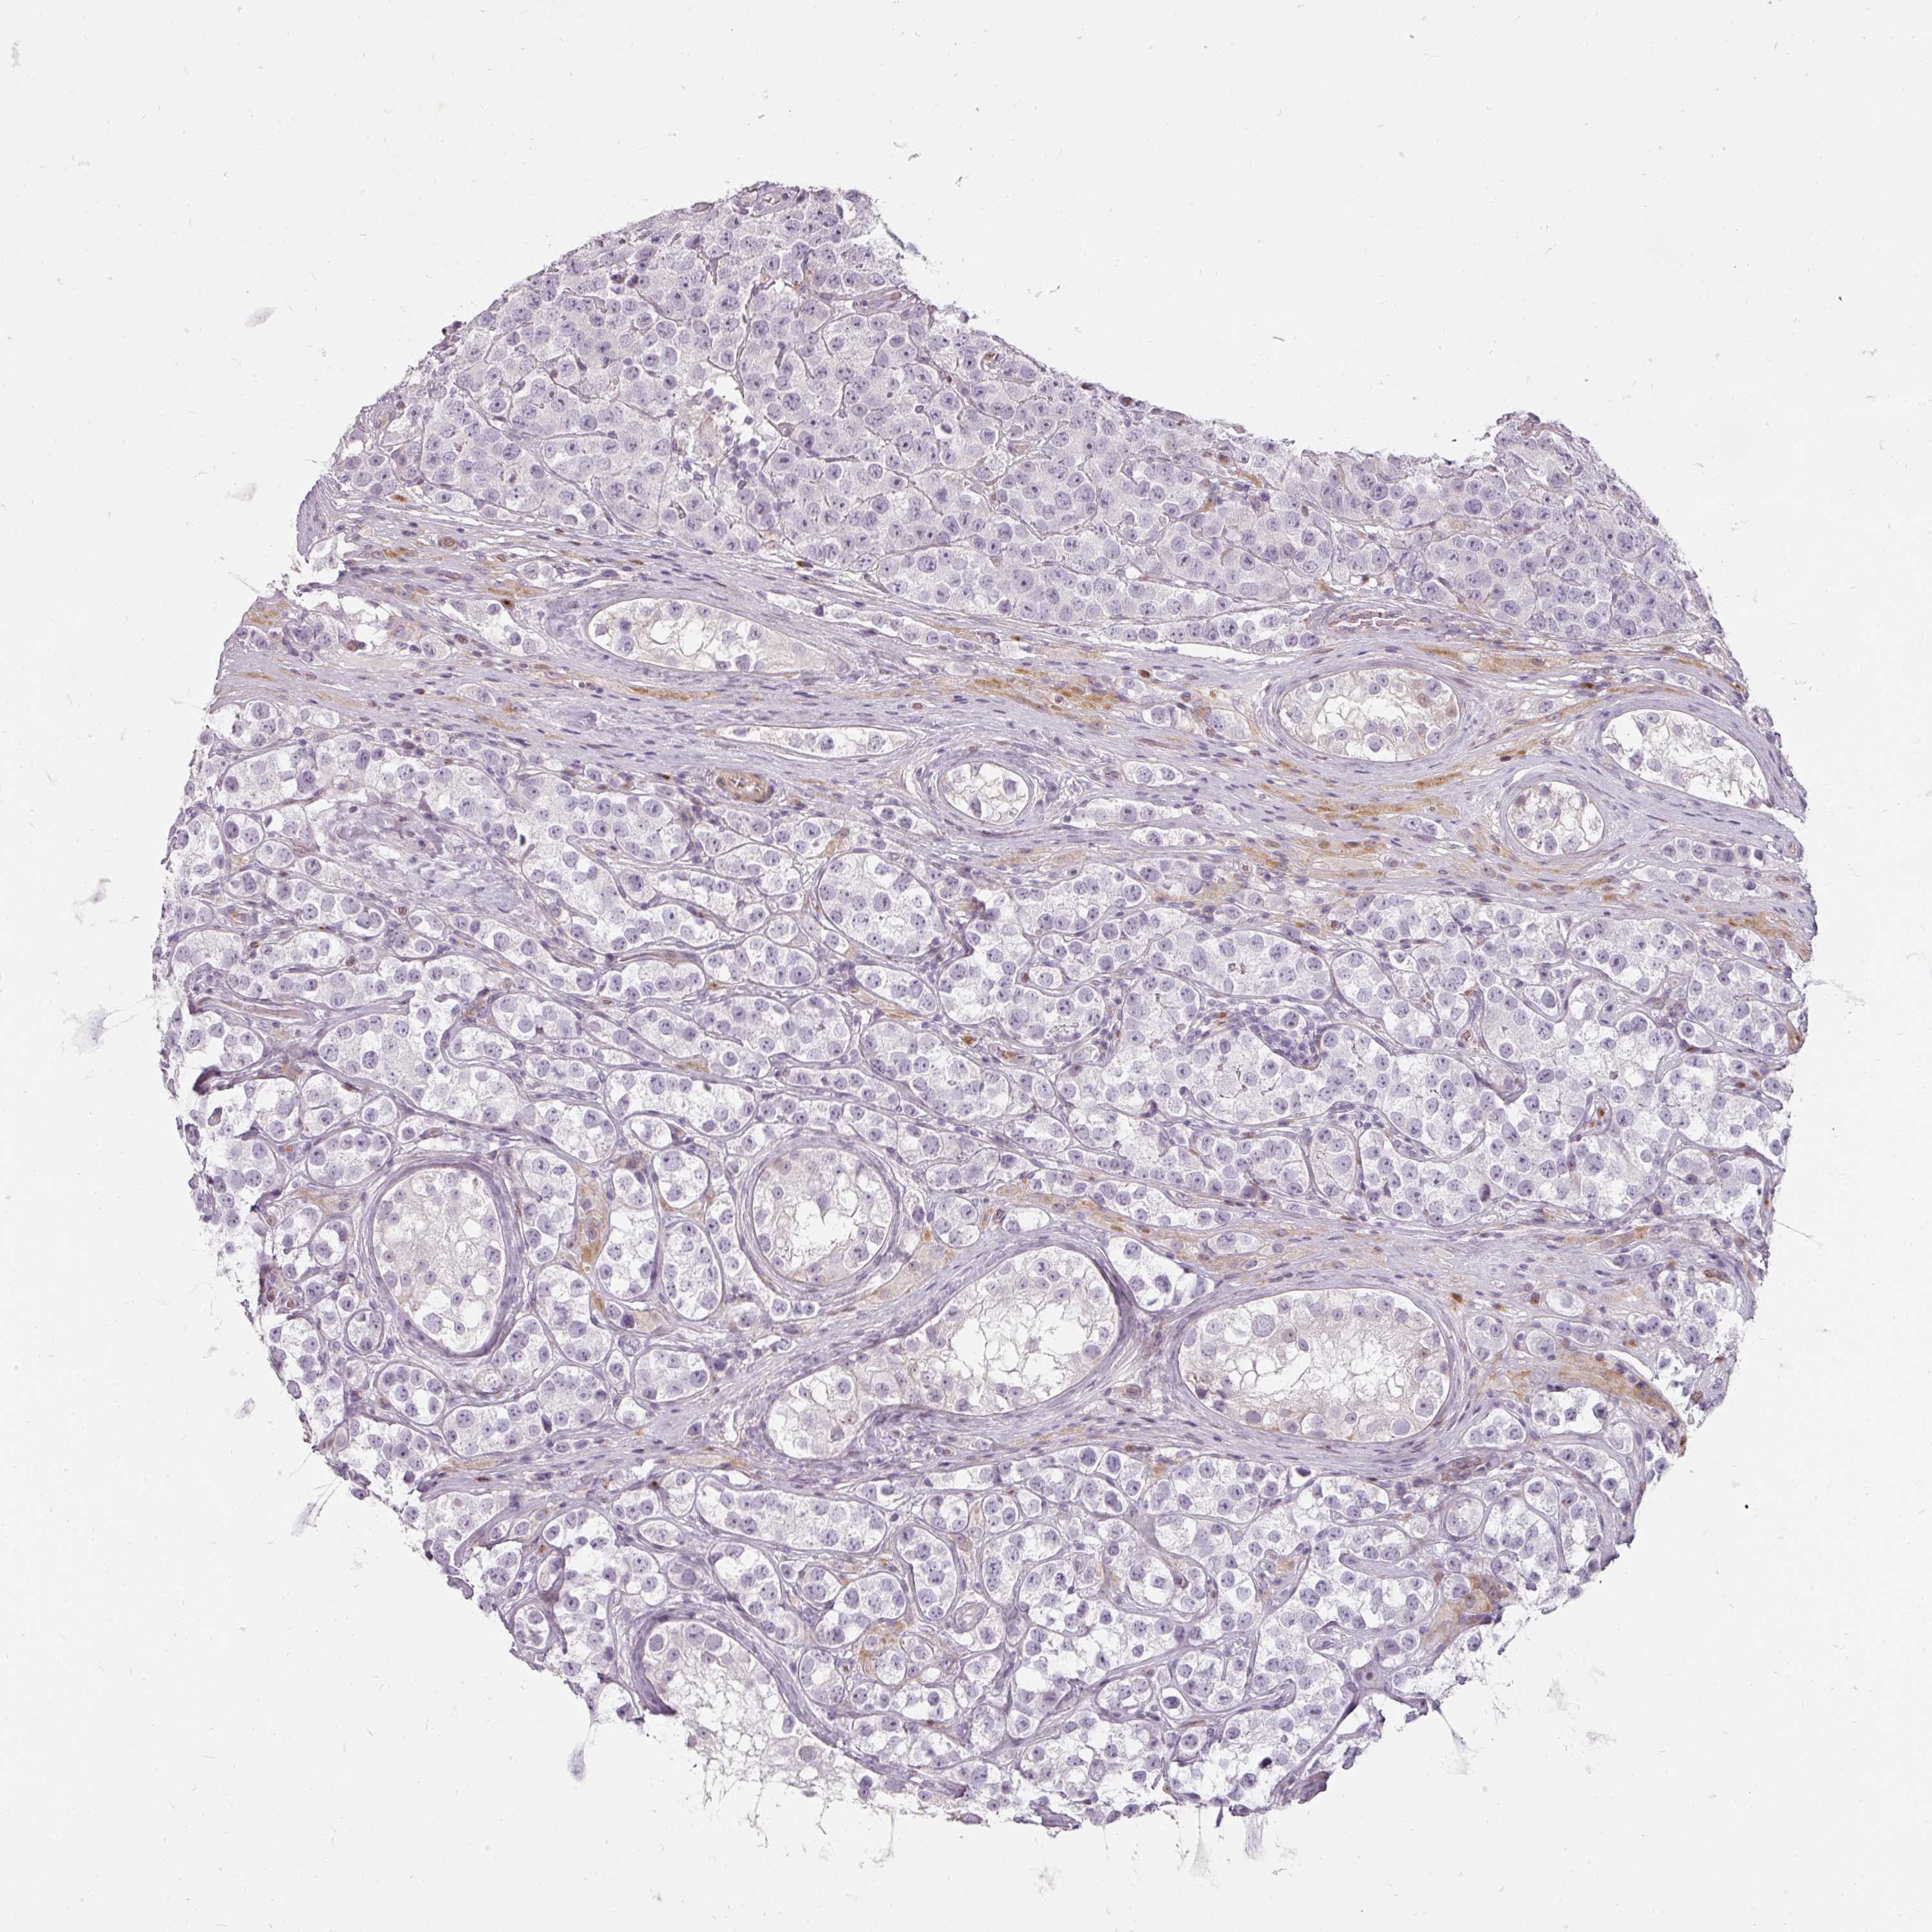

TESTIS CANCER - Protein expressioni

A mouse-over function shows sample information and annotation data. Click on an image to view it in a full screen mode. Samples can be filtered based on level of antibody staining by selecting one or several of the following categories: high, medium, low and not detected. The assay and annotation is described here.

Note that samples used for immunohistochemistry by the Human Protein Atlas do not correspond to samples in the TCGA dataset.

Antibody stainingi

Antibody staining in the annotated cell types in the current human tissue is reported as not detected, low, medium, or high, based on conventional immunohistochemistry profiling in selected tissues. This score is based on the combination of the staining intensity and fraction of stained cells.

Each image is clickable and will lead to virtual microscopy that enables deeper exploration of all samples and also displays staining intensity scores, fraction scores and subcellular localization as well as patient and tissue information for each sample.

Antibody HPA051360

Staining

High

Medium

Low

Not detected

Intensity

Strong

Moderate

Weak

Negative

Quantity

>75%

75%-25%

<25%

None

Location

Nuclear

Cytoplasmic/membranous

Cytoplasmic/membranous,nuclear

Carcinoma, Embryonal, NOS

Seminoma, NOS